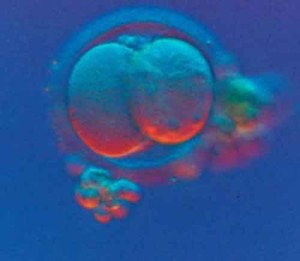

coltura-in-vitro